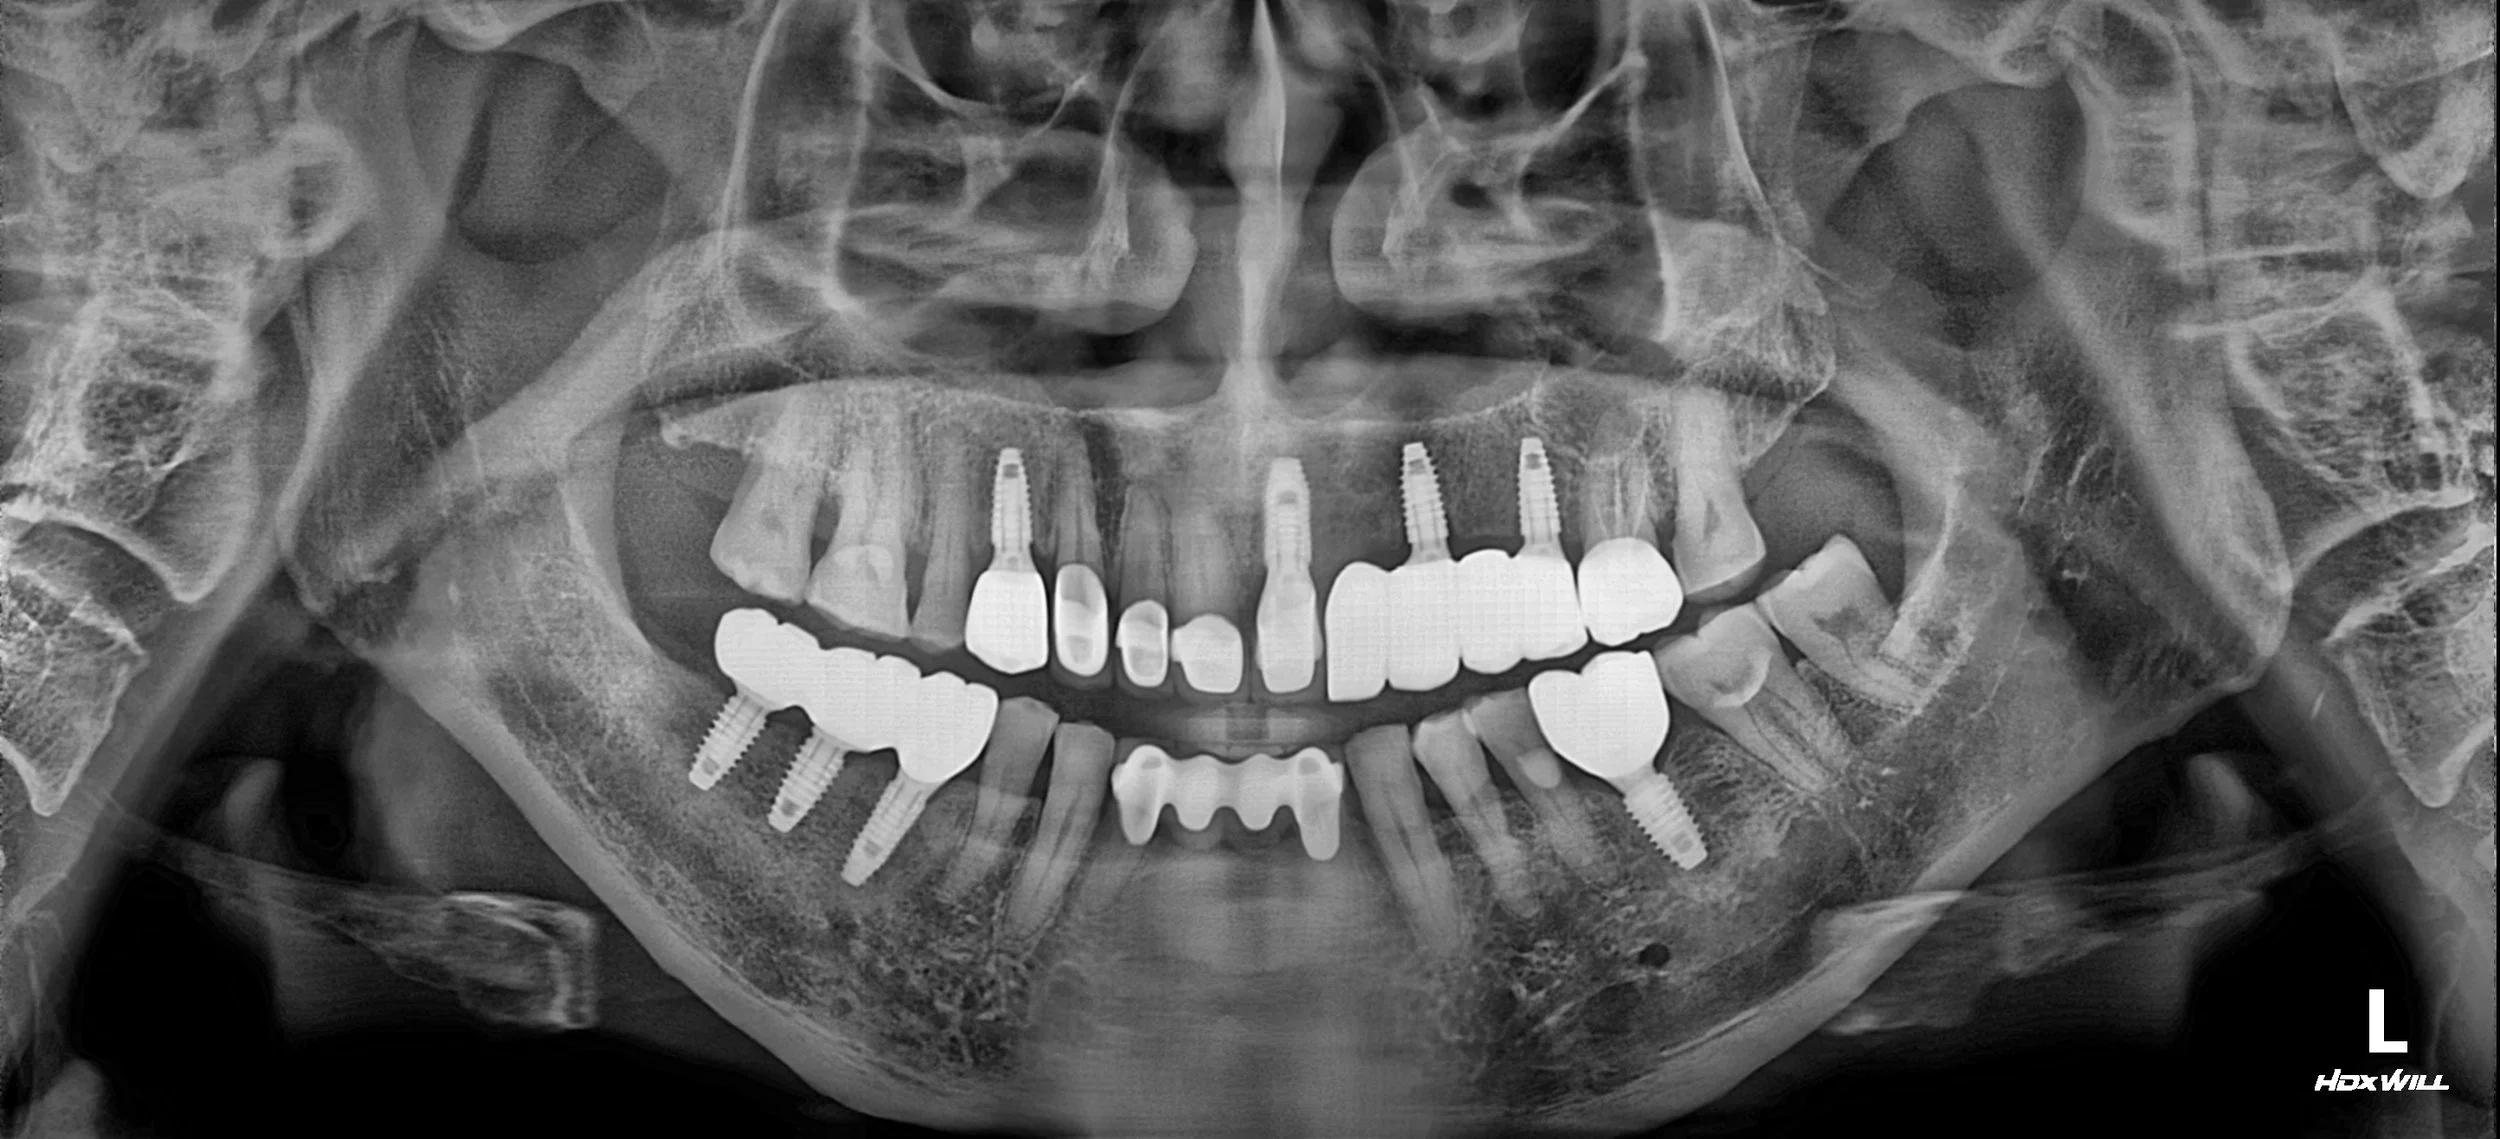

OPG - BEFORE

1. Occlusal Plane Re-establishment: Posterior support was re-established through strategic implant placement and crown restorations. By elevating the Vertical Dimension of Occlusion (VDO), we were able to "unlock" the trapped mandible.

2. Mandibular Repositioning: As the occlusal height was lifted, the mandible was guided to a more posterior and physiologically stable position. This effectively reduced the severity of the anterior deviation.